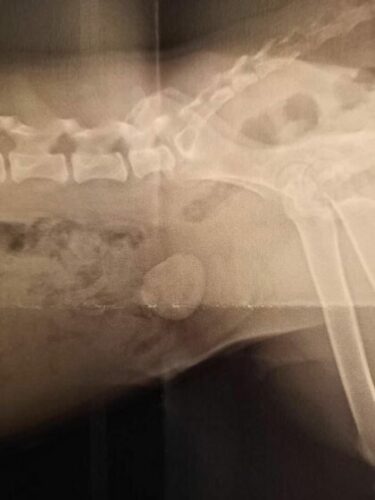

Echographie de la vessie.

Ce n’est pas qu’une infection urinaire.

Il faut opérer sans attendre.

Olga est une jeune chienne parfaite, ses problèmes urinaires, causes de son abandon sont rentrés dans l’ordre.

Il aurait suffit de presque rien, juste 500 e, pour payer l’opération de son énorme calcul et ne pas s’infliger la peine de devoir la quitter.

15 jours ont été necesssaires pour qu’ Olga puisse à nouveau être propre.

La mauvaise expérience d’ Olga, c’est peut être par rapport à sa propreté qu’elle l’a eue. … Lorsque le matin sa FA retrouvait des pipis dans la cuisine, la pauvre petite prenait un air contrit qu’on espère plus dû à l’estrême pudeur des chows qu’à un souvenir de réprimande. Avec un aussi gros calcul dans la vessie, il était impossible à Olga d’être propre.